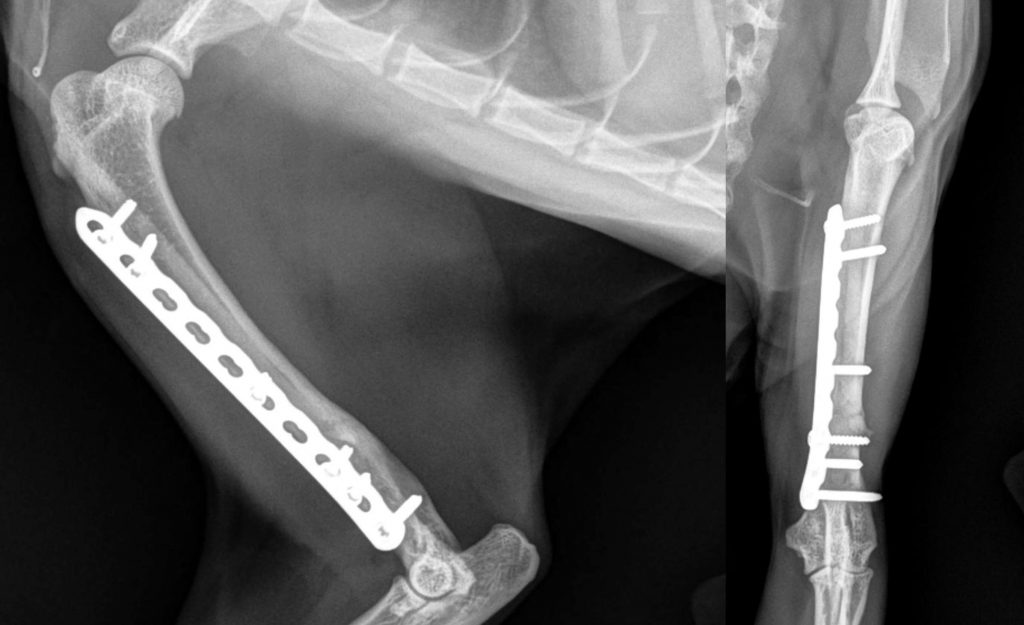

Las fracturas de hombro, entre las que se encuentran las llamadas fracturas de húmero proximal, son un tipo de fractura osteoporótica que representan alrededor del 6% de todas las fracturas del adulto, siendo la 4º fractura mas frecuente. Su incidencia está en aumento debido al aumento de la esperanza de vida de la población, por ello es necesario establecer claramente unas indicaciones para optar por el tratamiento quirúrgico o por el tratamiento conservador. Con esta finalidad hemos realizado recientemente una revisión sistemática publicada a finales del año 2020 en la revista internacional Journal Of Orthopaedic Surgery and Research que os adjuntamos.